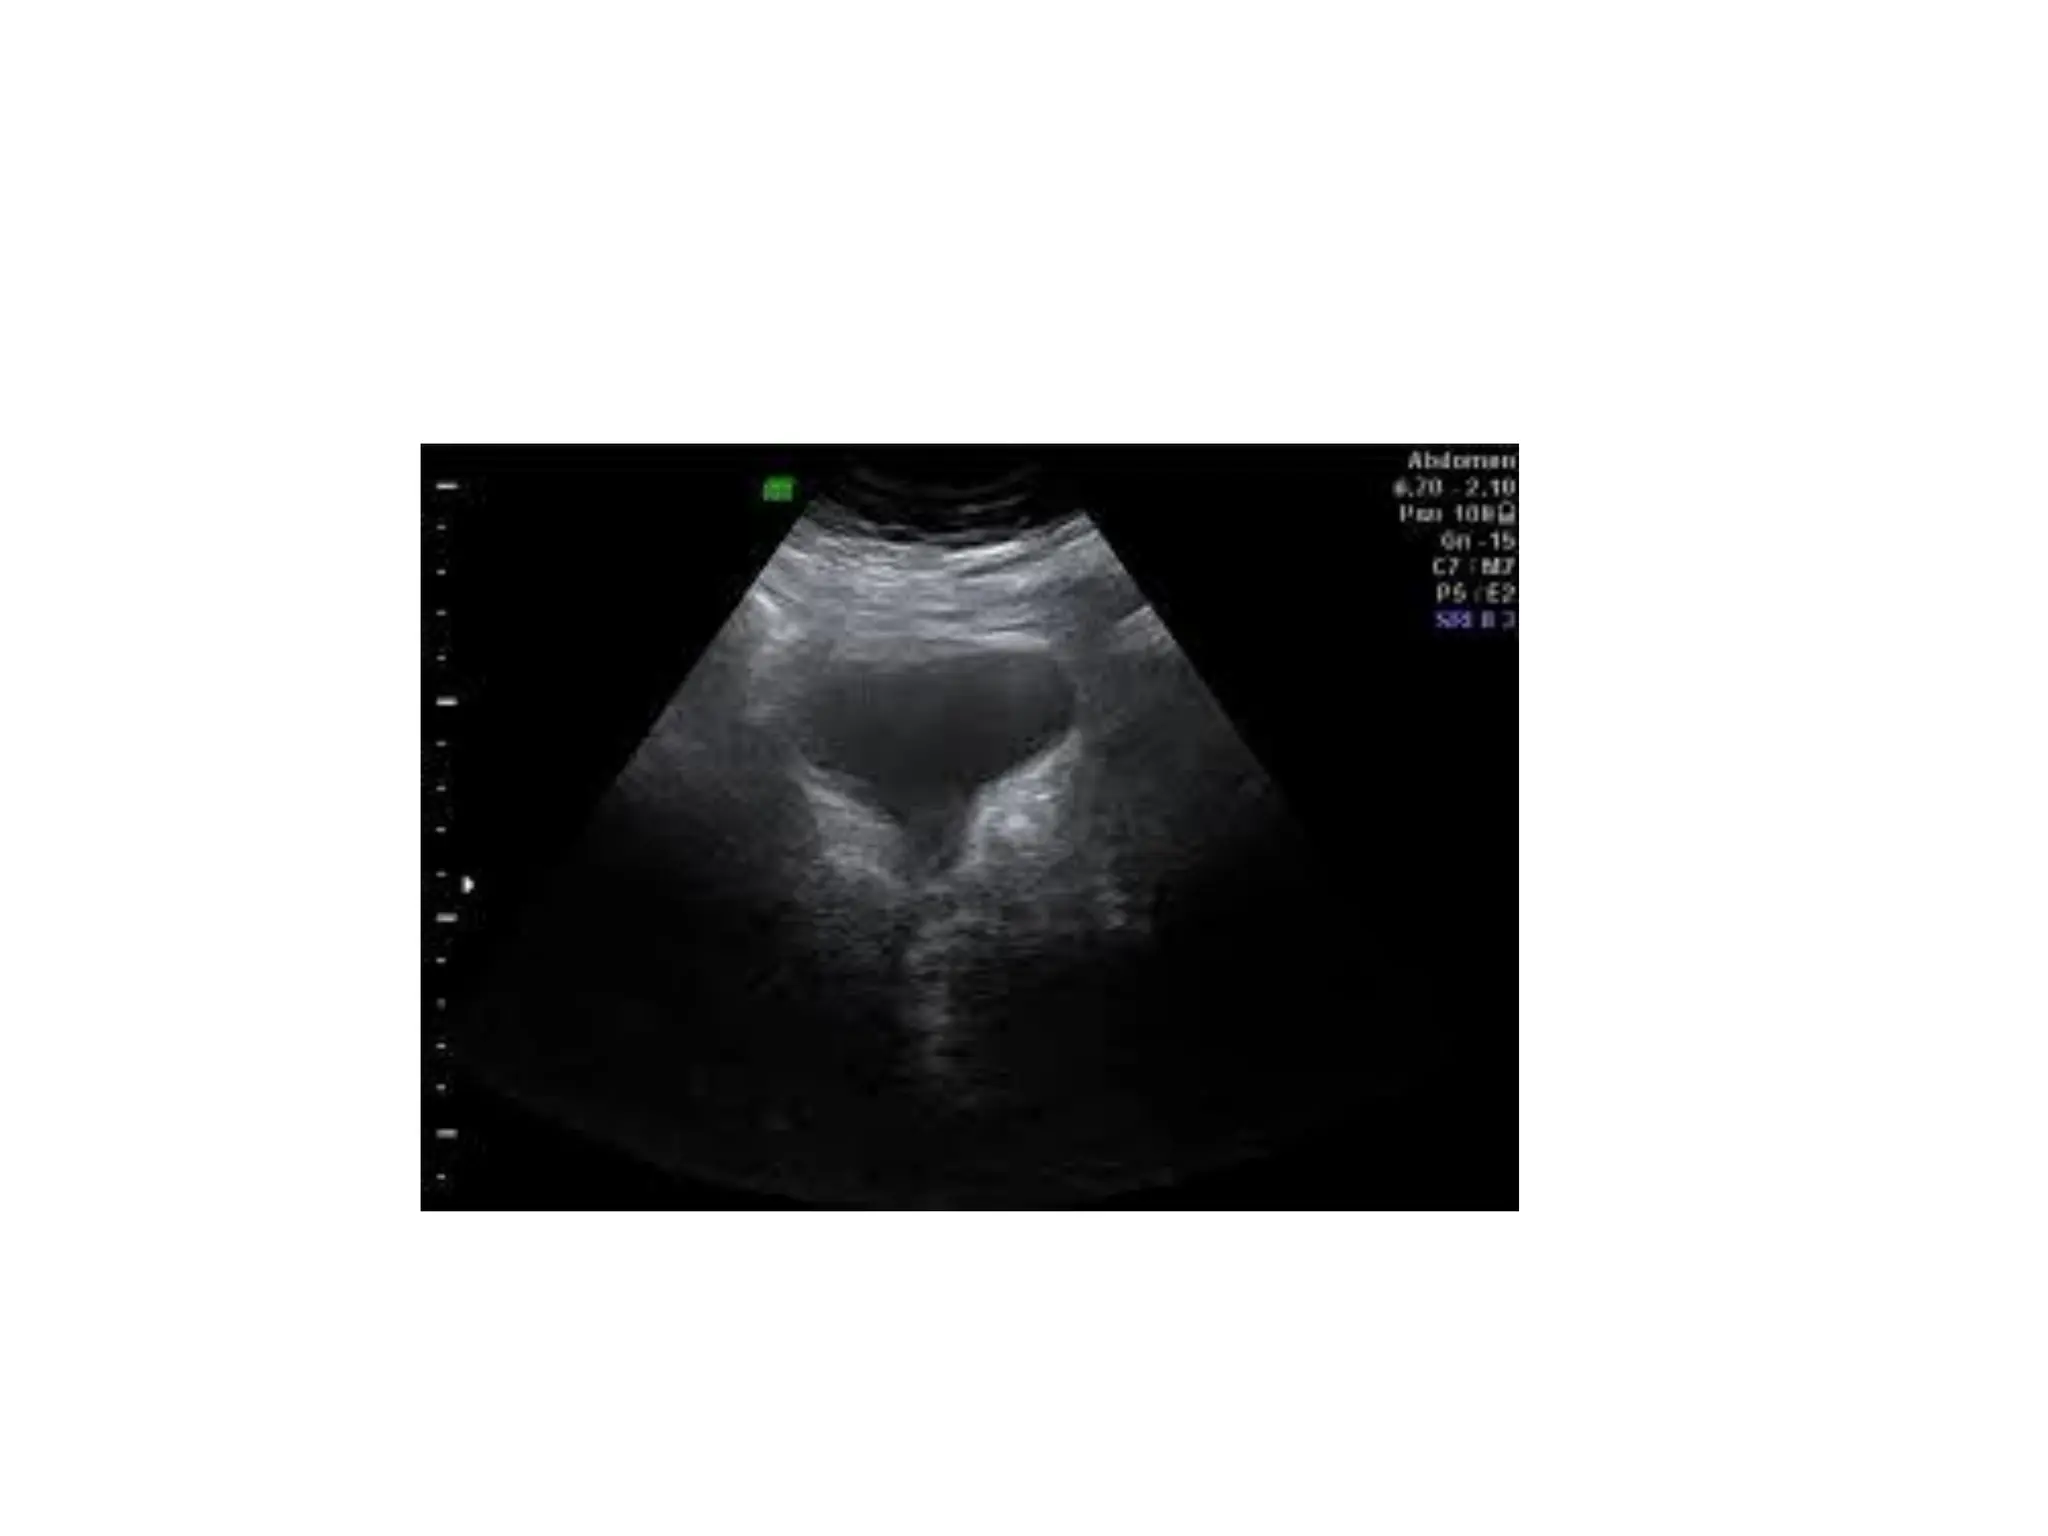

Gallbladder and biliary tract

To detect gallstones and blockages in the bile

ducts

Liver, spleen, and pancreas

• To detect tumors

USG Can beused to evaluate………

Gallbladder and biliarytract To detect gallstones and blockages in the bile ducts

Liver, spleen, andpancreas • To detect tumors